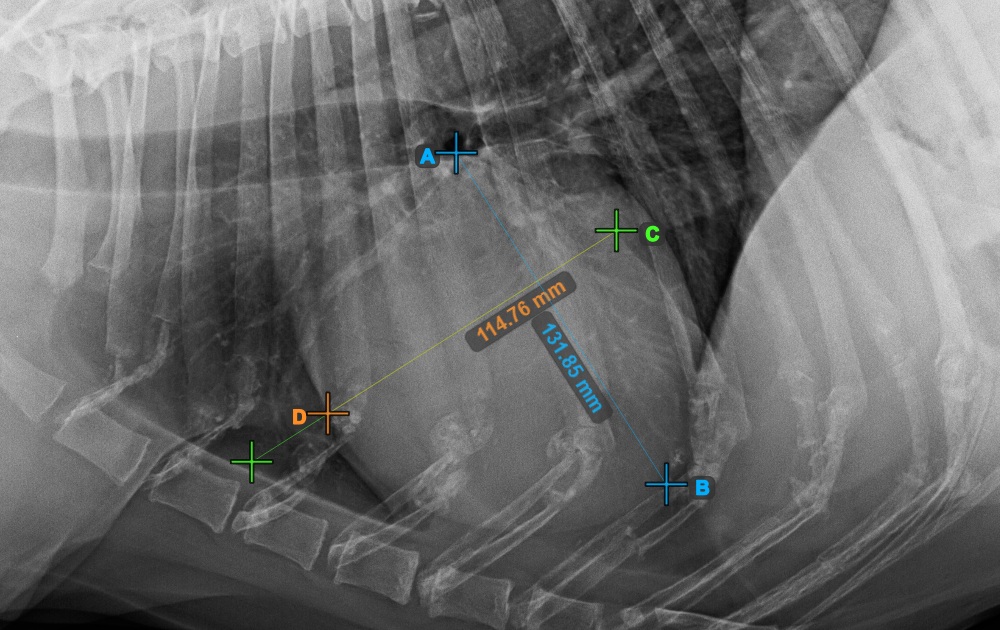

Indítsa el a mérést a Bifurcatio tracheae megjelölésével, a szív felső részéhez közel.

Az alábbi kép a Bifurcatio tracheae pont tipikus elhelyezkedését mutatja.

Fejezze be a szív hosszanti tengelyét az Apex pont megjelölésével, a szív alsó részéhez közel.

Az alábbi kép az Apex pont tipikus elhelyezkedését mutatja.

Folytassa a mérést a szív rövid tengelyének legszélesebb jobb (feji) pontjának megjelölésével.

Az alábbi kép a szív rövid tengelyének „legcranialisabb” pontjának tipikus elhelyezkedését szemlélteti

Fejezze be a szív rövid tengelyét a legszélesebb bal (caudal) pont megjelölésével.

Az alábbi kép a szív rövid tengelyének „legcaudalisabb” tipikus elhelyezkedését mutatja.